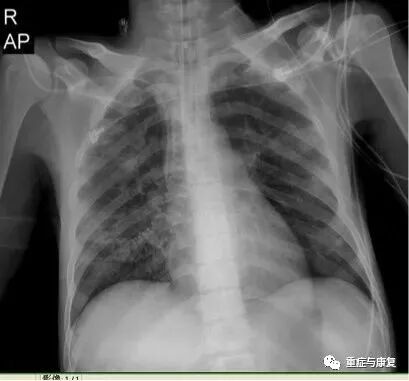

床边胸片(06-04):双肺炎症,未除外右侧胸腔积液;卧位心影增大(图1-1)。

图1-1. 床边照片(2015-6-4)